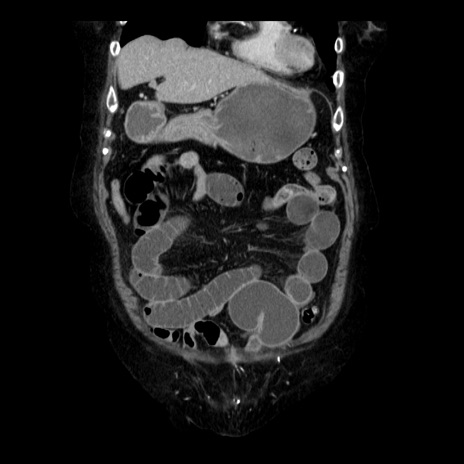

症例14(冠状断像)

【症例】 90歳代女性

【主訴】 腹痛・嘔吐

【現病歴】今朝から左側腹部痛を認めた。 経過観察していたが、嘔吐を認めたため来院。

【既往歴】 子宮癌術後

【身体所見】 意識清明、BP 127/54mmHg、P 98bpm Sp02 95%(RA)、BT 35.8°C、腹部平坦・軟腸ぜん動音聴取良好、右下腹部圧痛(+) 反跳痛なし

【データ】WBC 9800、CRP 0.46